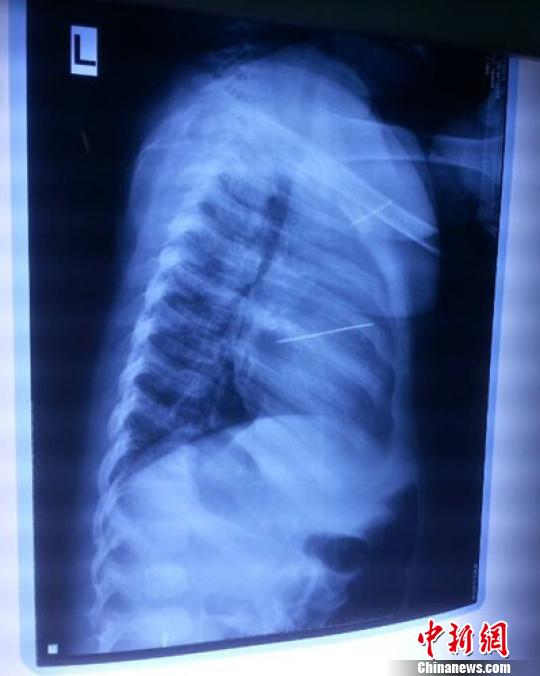

女嬰胸片提示心臟里面扎了一個(gè)縫衣針 蔡迅翔 攝

醫(yī)院胸心外科主任翟波介紹說,1月22日,小患者彤彤因?yàn)榘l(fā)燒抽搐來醫(yī)院就診,常規(guī)檢查時(shí)發(fā)現(xiàn)孩子心臟里面扎了一個(gè)縫衣針。

“第二天上午,我們做了個(gè)緊急彩超檢查,發(fā)現(xiàn)針是從患者右心室表面刺入,穿破室間隔,到達(dá)左心房,中間還有一部分損害到二尖瓣。于23號下午,我們就做了一個(gè)緊急手術(shù),手術(shù)中發(fā)現(xiàn),這枚針已經(jīng)刺入心臟,沒入了右心室的下面,表面已經(jīng)看不到針了,僅能看到一個(gè)小針眼,還在往外滲血,一點(diǎn)一點(diǎn)的滲,心包腔里面大概有100多毫升的出血,心包上一個(gè)洞,針在右心室表面刺入以后,穿過室間隔,在二尖瓣的上方,進(jìn)入了左心房,在針的四周,有很多纖維沉積物,包繞著這枚針。”翟波說,他們把針取出來以后,測量了一下,長度大概是五厘米,同時(shí)發(fā)現(xiàn)這個(gè)針給患者左心房的后壁造成了一定的損傷,左心房的后壁已經(jīng)損傷了三分之二,還剩下有左心房的外膜,很薄的一層,如果這一層再破的話,這個(gè)孩子將會引起大出血,很快就會死亡。